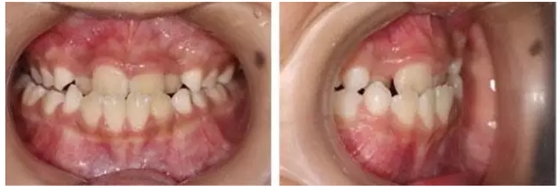

正常前牙咬合關系,是上前牙覆蓋在下前牙的前面。如果出現(xiàn)相反的現(xiàn)象,即下前牙位于上前牙的前面,就是人們常說的“地包天”,醫(yī)學上稱之為前牙反頜。“地包天”,是口腔錯頜畸形的一種疾病,是我國兒童常見的一種錯頜畸形,對口腔功能、顏面美觀和心理健康有較嚴重的影響,并且隨著患者的生長增齡癥狀逐漸加重。

“地包天”會造成患者口腔功能異常,包括咀嚼效率下降,咬合創(chuàng)傷等等。而且,嚴重的患者常導致面部凹陷,下巴明顯突出,表現(xiàn)為“月牙臉”,對患者美觀影響較大,繼而可導致相應的心理問題,影響患者的正常工作學習生活。